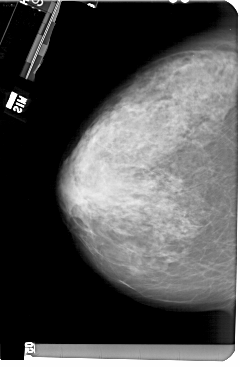

A_1504_1.LEFT_CC

LEFT_CC LINES 5491 PIXELS_PER_LINE 3586 BITS_PER_PIXEL 12 RESOLUTION 43.5 NON_OVERLAY